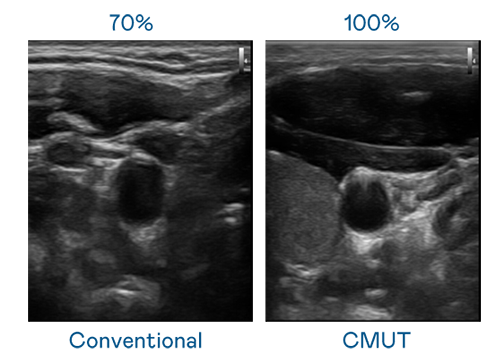

CMUT 技术是一种用电容式微机电元件来产生超音波讯号的技术。与传统 PZT 压电式技术相比,CMUT 频宽增加 30%,更宽频的超音波讯号让影像解析度大幅提升,是实现高影像品质医疗超音波扫描、促进精准医疗发展的关键技术。

超音波影像的解析度高低,首先取决于探头能发出的讯号频宽。70net永乐高 CMUT 可提供高清晰的超音波讯号,提供高频宽、高灵敏度、影像纹理细节更高的超音波影像,协助医护人员缩短影像判读时间及利用精准的医疗影像进行诊断。